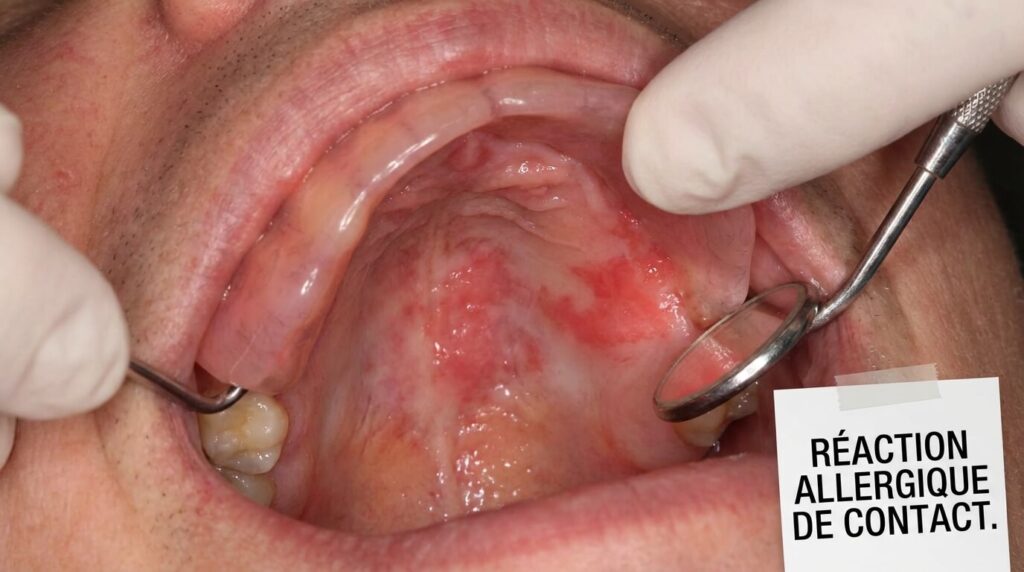

Le tableau clinique le plus fréquent est la stomatite prothétique allergique.

- Rougeur (Érythème) : La gencive ou le palais dessine exactement la forme de l’appareil en rouge vif, comme une « empreinte ».

- Sensations : Le patient décrit une bouche « en feu », des picotements, une sécheresse intense ou un goût amer/métallique permanent.